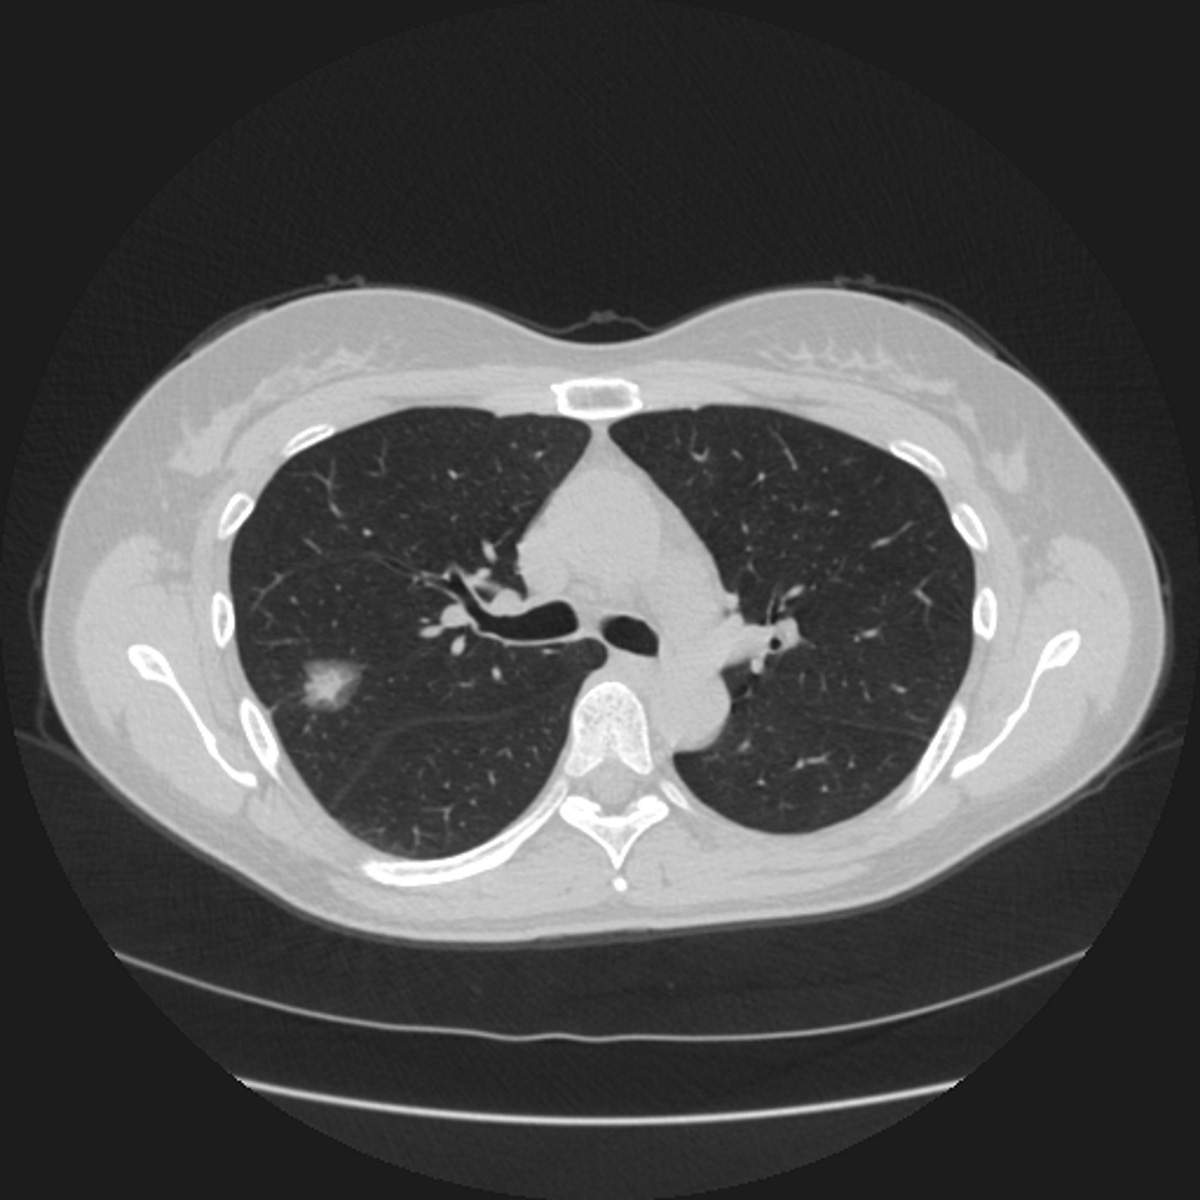

Now, radiologists can achieve newfound Certainty of Search using the ClearRead CT technology, the only Clear Visual Intelligence solution with our unique suppression technology. It removes the vessels and machine noise on the chest CT image, providing an unimpaired view of the chest for efficient and accurate detection of cardiothoracic diseases. ClearRead CT is a natural addition for opportunistic CAC and nodule detection or as part of a lung cancer screening program.